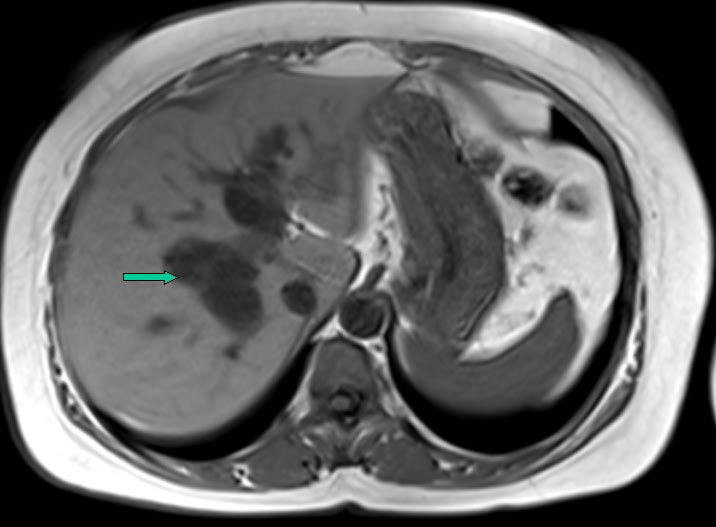

From mricases.blogspot.com

mricases Choledochal cyst Type IV MRI features Type Ic Choledochal Cyst Type i cysts are a dilatation of the extrahepatic bile duct. A choledochal cyst (cc) or biliary cyst is a congenital or acquired anomaly affecting the biliary tree. Biliary cysts, also termed choledochal malformations, are cystic dilations that may occur singly or in multiples throughout. Characterized by fusiform dilation of the extrahepatic bile duct. Choledochal cyst is a congenital cystic. Type Ic Choledochal Cyst.